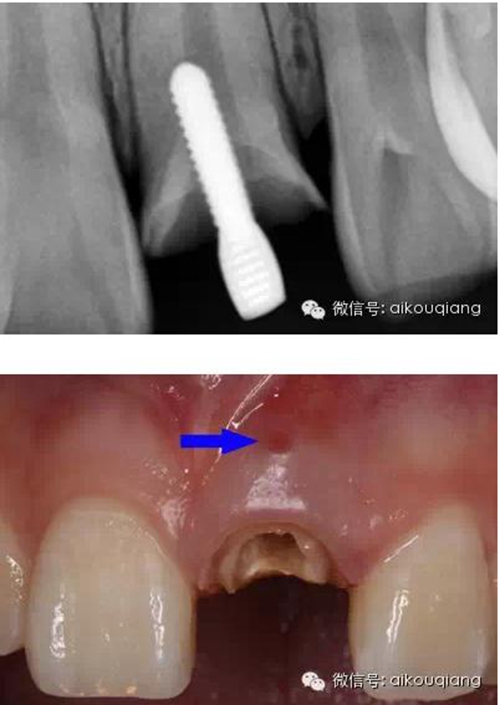

X片

瘺管部位

瘺管位置